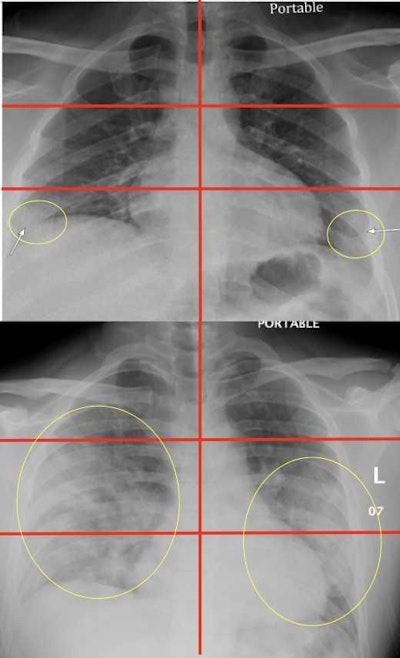

The researchers developed an x-ray scoring system to evaluate COVID-19 disease severity in order to better determine which patients need to be hospitalized and/or intubated.

The team reviewed race and information on preexisting conditions on each patient, analyzed the x-rays for COVID-19 patterns, and divided them into six zones: upper right, upper left, middle right, middle left, lower right, and lower left. They then developed a scoring system from 0 to 6 to measure disease severity (lower severity scores, 0 to 2; higher scores, 3 to 6). Higher severity scores corresponded with lung involvement in multiple areas.